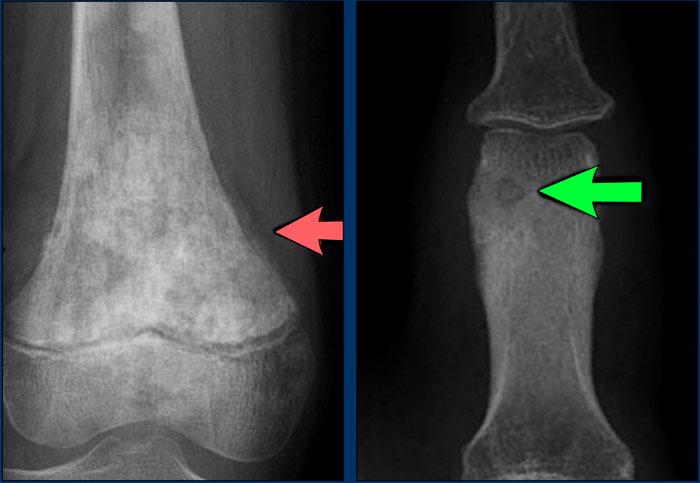

Images

- Osteosarcoma

Irregular cortical destruction - Sarcôm Ewing

Phá hủy vỏ xương (mũi tên xanh) và phản ứng màng xương xâm lấn (đầu mũi tên).